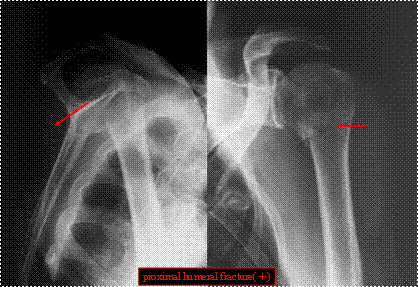

診療放射線技師画像読影レポーティング・・・骨折を知ろう・・・

“画像読影レポーティングすることで撮影技術がアップする!“